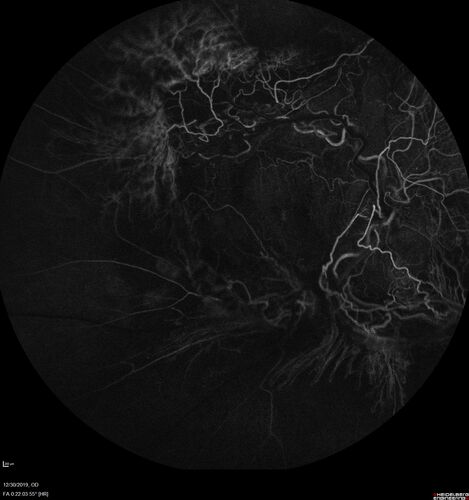

Severe diabetic tractional retinal detachment one year following diagnosis of type II Diabetes Mellitus

44 year old man The vision in the left eye started to decline about 4 days ago.  Prior to that the left eye was the better eye.  He was diagnosed with diabetes a year ago.

VA OD: Dcc20/50-1 OS: Dcc20/125-2, TP: OD:12 OS:13

Following two surgeries in each eye, silicone oil remaining forever, monthly anti-VEGF for severe DME - BCVA OU 20/200 at 3 years